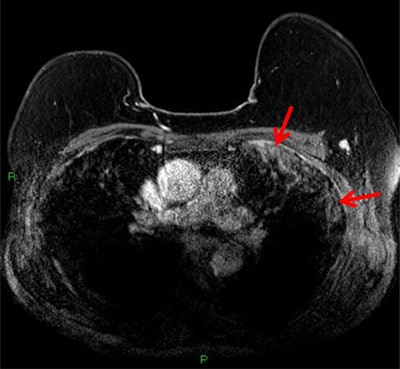

T2-weighted MRI depicting subpleural high T2 signal intensity (red arrows). All images courtesy of Dr. Anmol Malhotra.